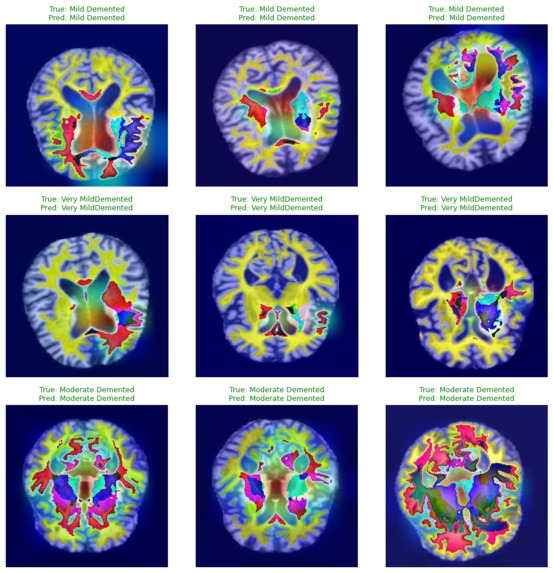

Alzheimer_MRI is a deep learning–based system that classifies brain MRI images into four stages of Alzheimer’s disease: Non-Demented, Very Mild Demented, Mild Demented, and Moderate Demented. The model processes MRI scans and predicts the disease stage, providing quantitative evaluation metrics to assess classification performance.

The project was built using a PyTorch-based pipeline. MRI images were preprocessed through resizing and normalization, and the dataset was split into training, validation, and testing sets using stratified sampling. A pretrained Xception convolutional neural network was used as the backbone through transfer learning, with custom classification layers added for four-class prediction. The model was trained using the Adamax optimizer and cross-entropy loss, and evaluated using accuracy, confusion matrices, and multi-class ROC–AUC scores.

One major challenge was distinguishing between early-stage Alzheimer’s classes, where MRI structural differences are minimal. Another challenge was ensuring a clean transition from high-level frameworks to PyTorch, especially managing tensor shapes, gradient flow, and reproducibility. Designing a fair evaluation strategy for multi-class medical data also required careful consideration.